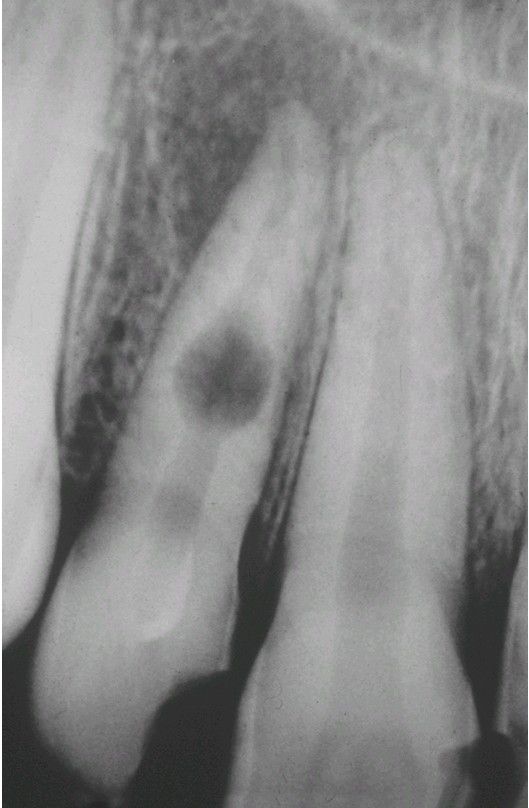

Internal resorption

Balloonlike enlargement of the root